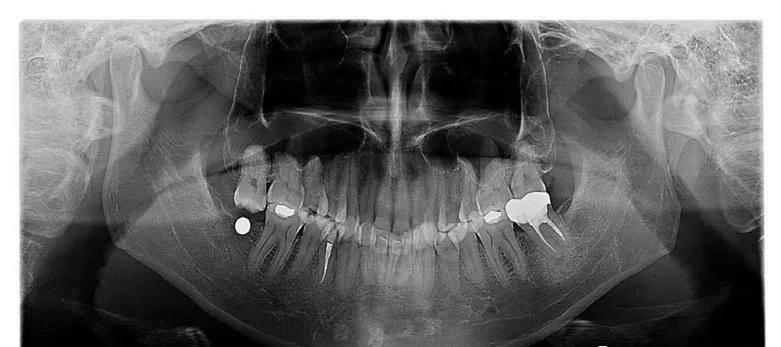

图8-20a缺牙间隙高度不够47缺失,但对颌牙伸长后,缺牙间隙只有2~3mm图